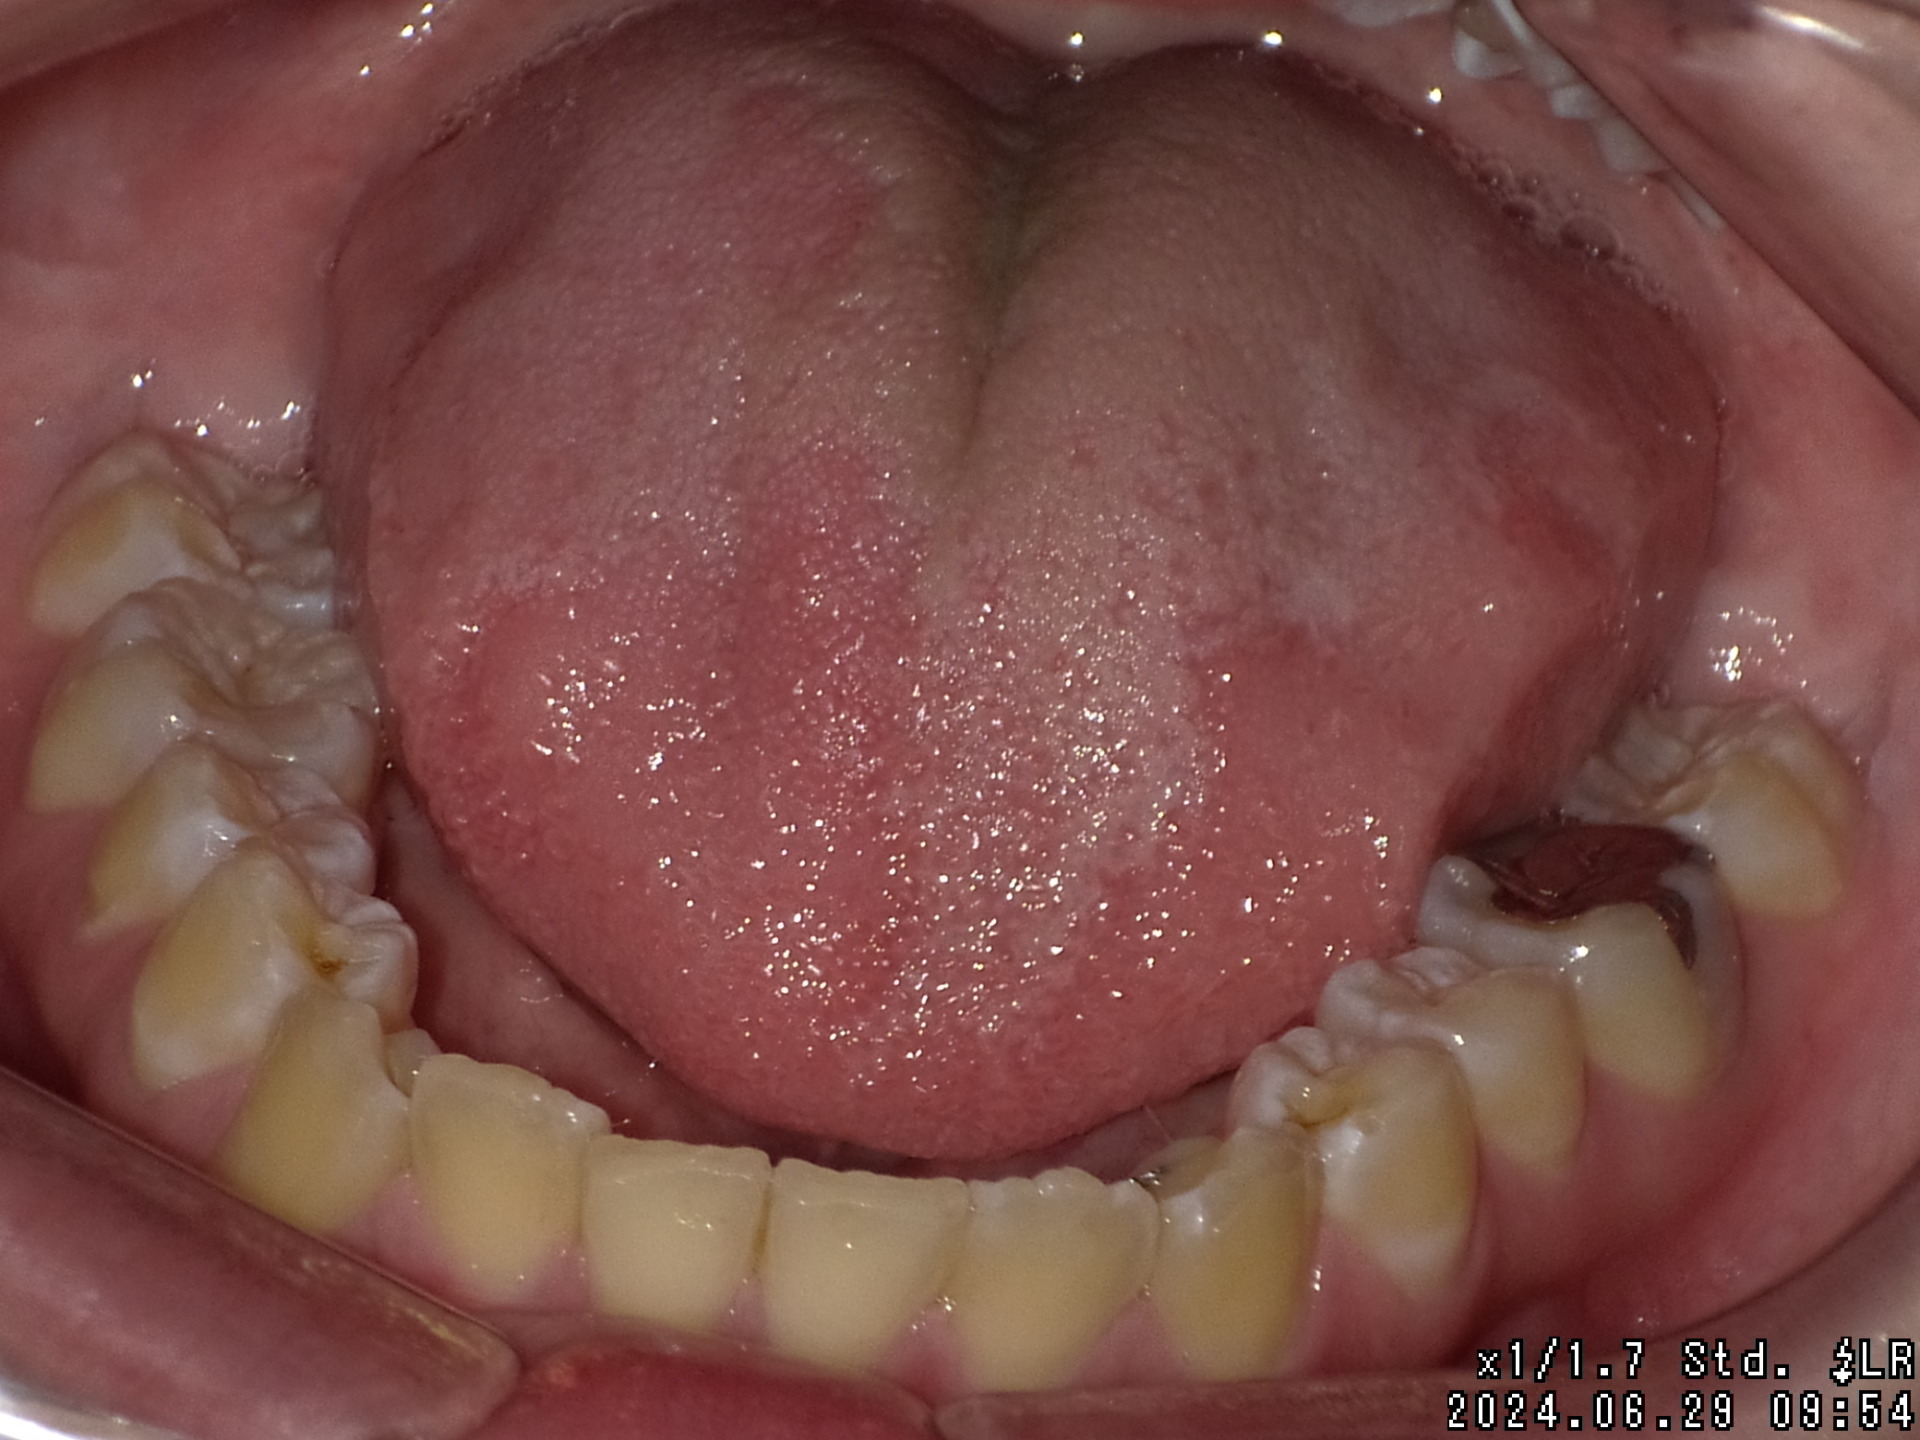

矯正後

| 症状 | 左上2番3番逆転症例 |

|---|---|

| 通院時の 年齢 |

10才2ヶ月〜21才2ヶ月 |

| 通院回数 | 142回 |

| 通院目的 | 永久歯を抜かずに歯並びを治したい。 |

| 処置内容 | プレート拡大処置・マルチブラケット装置・クリアアライナー・ディスタライザー |

| 費用 | 基本料金 税抜625,000円 (通院時2,100円〜4,400円の調整料を頂いていました。) ※過去の治療の料金ですので、現在とは異なります。 |

| デメリット・院長コメント | 永久歯を抜かない治療のデメリットは、治療期間が長いことです。 ただし、その後の人生の長さを考えると、健全な小臼歯を2本または4本抜歯の矯正治療よりも、はるかにメリットがあるといえます。 また、アーチが小さくならないので、舌が後ろに押し込まれないためいびき防止につながり睡眠の質の向上にもつながります。 |